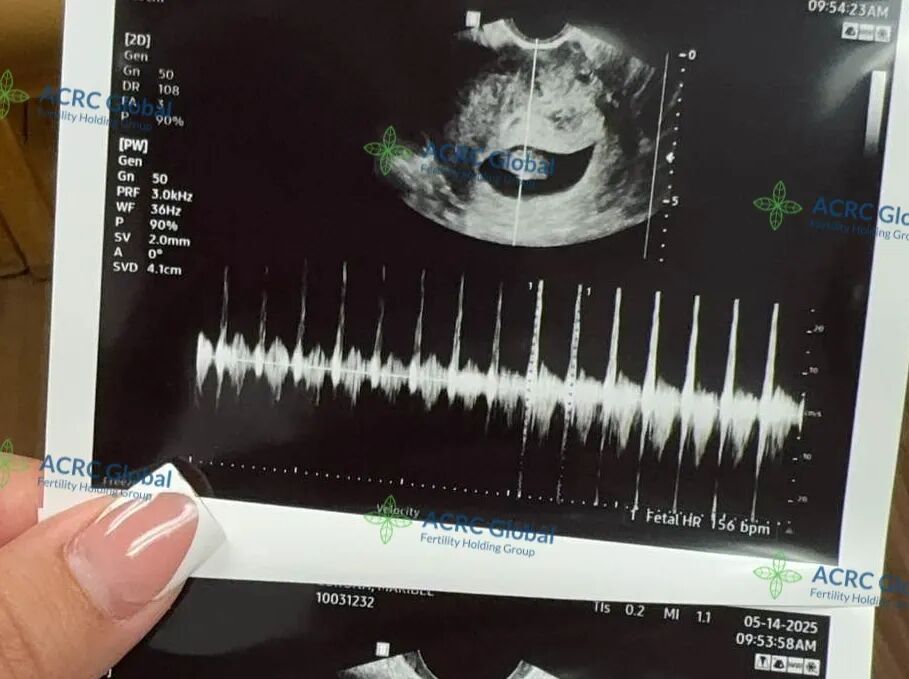

8周5天,胎心强劲

在顺利完成移植后,爱妈M迎来了首次B超检查,宝宝已经8周又5天,胎心强劲,达到176次/分钟,发育一切良好。感谢她的细心守护!

此次合作中,爱妈M匹配的是一位来自加州的单身准妈妈。这位准妈妈因为年龄因素更加珍惜这次成为母亲的机会,备孕之路走得格外用心与坚定。能够顺利进入孕期,是她多年来努力和等待的成果,也是一个梦想逐步成真的开始。